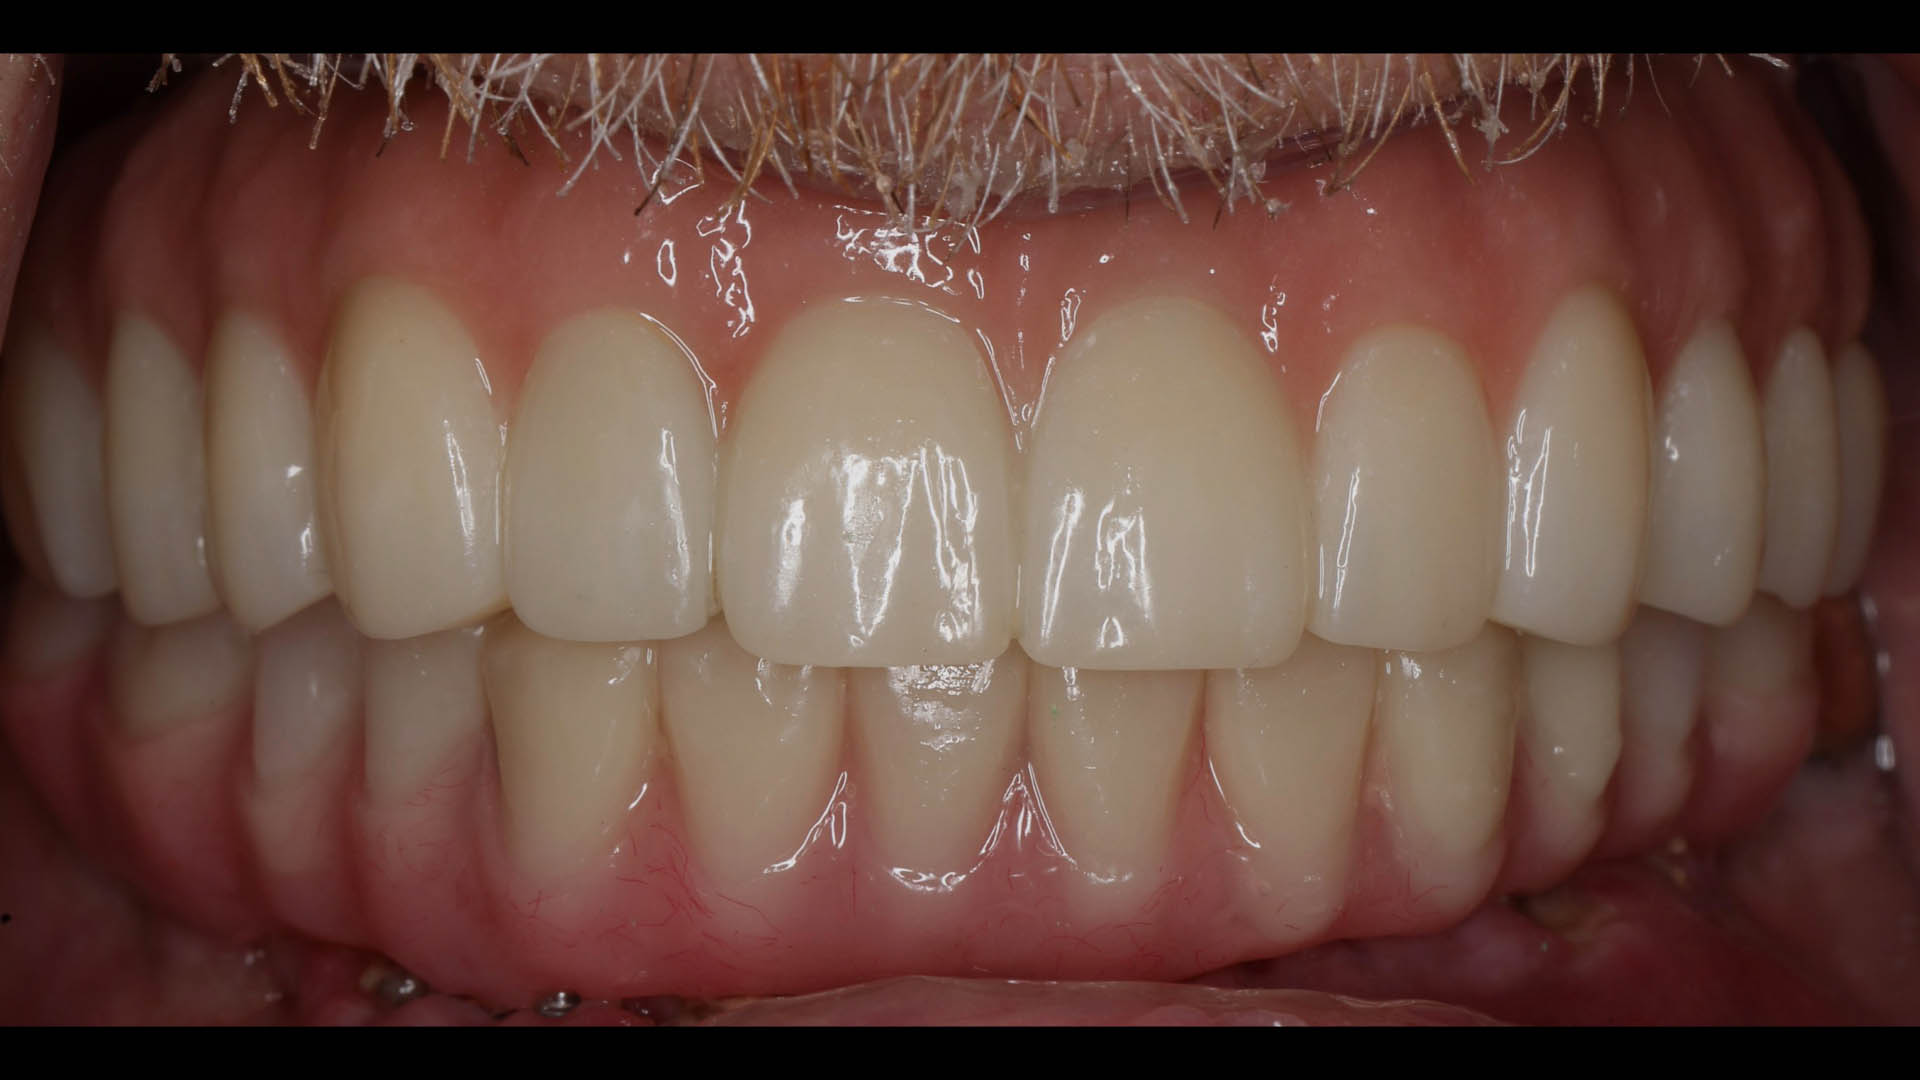

Take a glimpse into the magic of Coral Gables Dentistry through our before and after pictures. See firsthand the incredible smile makeover transformations that have brought confidence and joy to our patients.